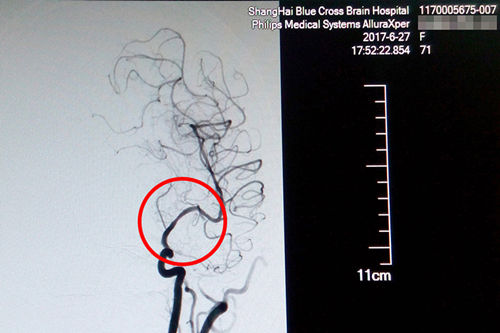

站在手術(shù)臺前的李主任,表現(xiàn)出的是與平日不同的冷靜和沉著。經(jīng)術(shù)中精準(zhǔn)測量發(fā)現(xiàn),患者盛阿姨血管狹窄達(dá)到了77%,血管非常狹窄,使放置球囊擴(kuò)張支架的難度更大。好在李主任積累了豐富的DSA手術(shù)經(jīng)驗(yàn),經(jīng)過仔細(xì)小心的操作,導(dǎo)絲成功地通過了狹窄的血管。李主任用他的“血管藝術(shù)”使瀕臨枯萎的血管重新綻放出了生命的活力,最終原本非常狹窄的血管腔順利張開了:“……將球囊擴(kuò)張支架置入狹窄處,觀察后準(zhǔn)確釋放球囊擴(kuò)張支架,再造行3D造影,顯示血管擴(kuò)張,血流恢復(fù)正常。(摘自術(shù)后小結(jié))”。

術(shù)后DSA影像顯示,患者血管狹窄部位血流恢復(fù)正常

就這樣,這臺DSA手術(shù)又一次獲得了成功,術(shù)后CT復(fù)查無出血,患者恢復(fù)情況良好,這才出現(xiàn)了本文開頭的感人一幕。原本大面積腦梗、病情兇險的的盛阿姨在李主任和團(tuán)隊的努力下,通過DSA球囊擴(kuò)張支架置入術(shù),平安度過了生命中的一個轉(zhuǎn)折點(diǎn)。隨后,在不到一個月的時間里,她的語言功能已逐漸恢復(fù),四肢肌力已經(jīng)接近正常水平,目前正在積極接受康復(fù)治療中。